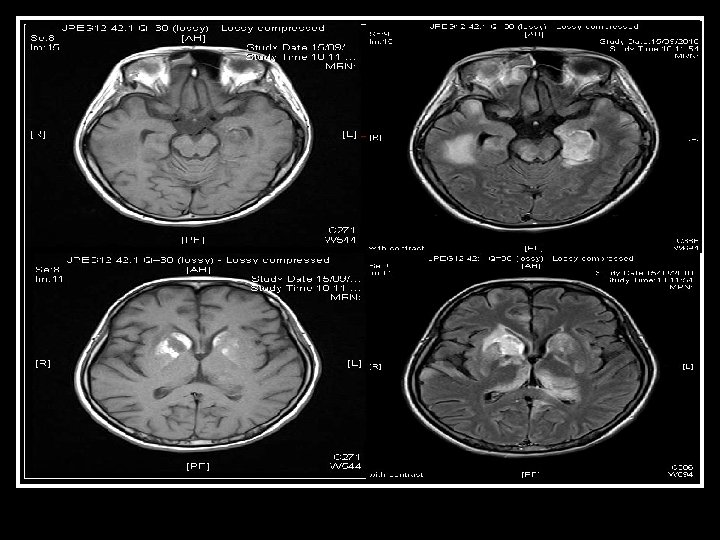

(4) Neurologist assessment: summary Initial presenting illness n Bulbar palsy with normal NCT, but clinically nil response to IVIG and steroid Deterioration right now n Cerebral dysfunction with raised CSF protein n Hypointensities in bilateral temporal and Rt BG Need to consider other diagnosis n Sinusitis with orbital + CNS extension n For contrast MRI brain + skull base

Searching for an answer, again…. . n n n n n 9 th July: Plain CT Brain (Hospital A) 7 th Aug: Plain CT Brain (Hospital A) 25 th August: Plain CT Orbit (Hospital A) 27 th August: Contrast CT brain + Sinus 4 th September: MRI brain + brainstem 4 th September: Plain CT brain 10 th September: Contrast CT brain 11 th September: Plain CT sinus 15 th September: MRI brain + DWI

Brain was so ill, but no answer…. Condition since 4 th September 2010 n Multi-focal inflammatory change over bilateral basal ganglia/ thalamus/ temporal lobes and brainstem on MRI, unlikely due to bacterial infection n GCS E 4 Vt. M 1 and all limbs flaccid n Persistent high fever and tachycardia despite Vanco/netro/fluconazole 14 days

Summary of progression • June/ 2010 n • July/ 2010 n • Early Aug/ 2010 n • Late Aug/ 2010 n • Sept/ 2010 n Lt face weak Bulbar palsy Dilated Rt pupil and uveitis Endophthalmitis and high fever Deep coma, tetraplegia, high fever n n n Nil imaging Facial neuritis Bilateral basal ganglia change Bilateral temporal + BG + thalami + pons